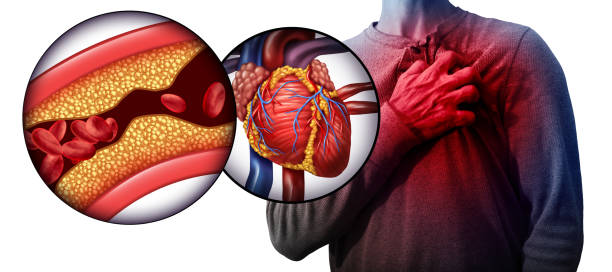

I am Dr. Hamid Raza, a dedicated Homeopathy Physician with extensive experience in treating complex health conditions through natural and holistic approaches. Specializing in heart, lungs, and kidney disorders, I am committed to restoring health and balance in patients with both acute and chronic illnesses. My practice also includes the effective management of serious conditions such as cancer, dengue, and other critical diseases, offering personalized care that targets the root cause rather than just the symptoms. With a patient-centered approach, I strive to provide safe, gentle, and lasting healing solutions.

I am Dr. Hamid Raza, a dedicated Homeopathy Physician with extensive experience in treating complex health conditions through natural and holistic approaches. Specializing in heart, lungs, and kidney disorders, I am committed to restoring health and balance in patients with both acute and chronic illnesses. My practice also includes the effective management of serious conditions such as cancer, dengue, and other critical diseases, offering personalized care that targets the root cause rather than just the symptoms. With a patient-centered approach, I strive to provide safe, gentle, and lasting healing solutions.